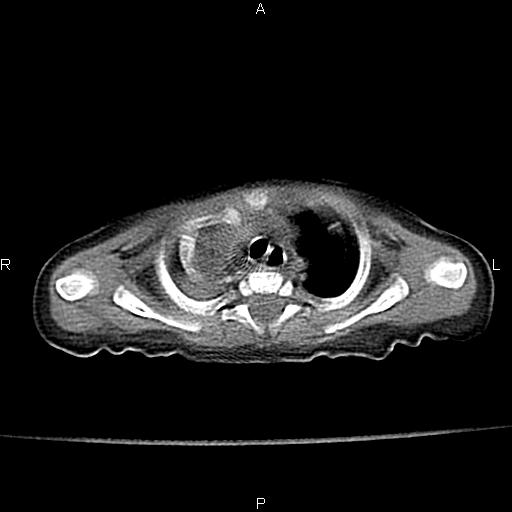

以下是引用jsdtd在2010-7-26 14:42:00的发言:[br]胸腺呈帆状,体位所致,没事。

以下是引用aa13877358820在2010-7-26 12:35:00的发言:[br]男性,三个月,卧位胸片,咳嗽、气促、发热14天,两肺闻及细小水泡音。[br]